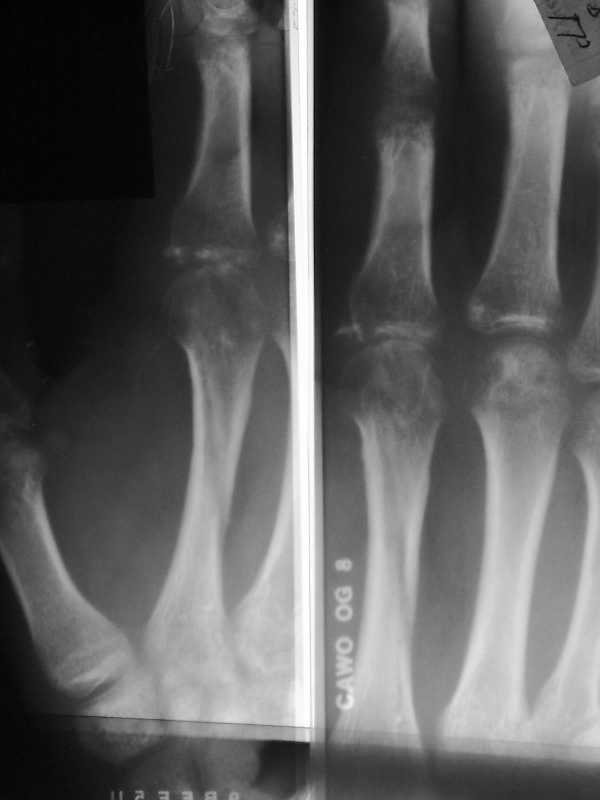

Опять болгарка

Изображение